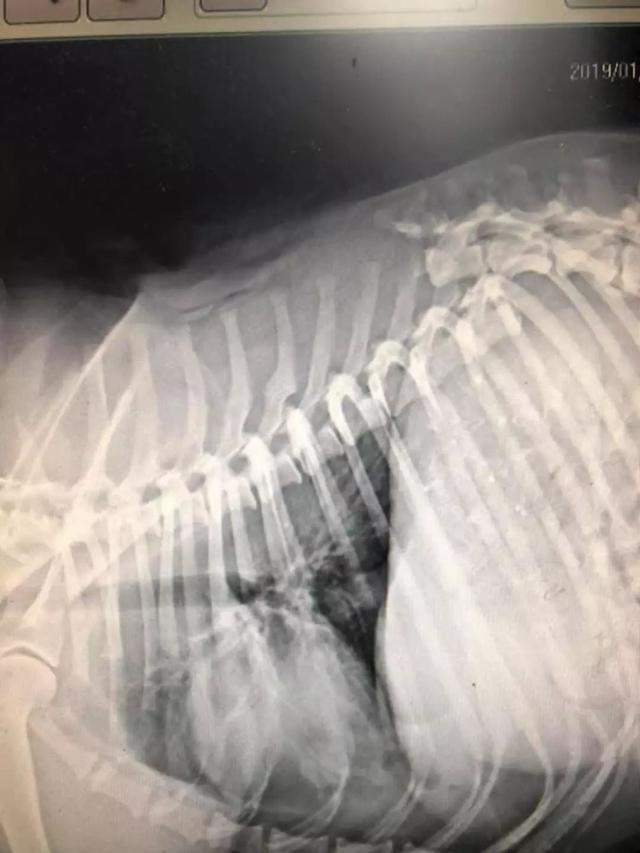

就在1月17日,大白不幸遭遇车祸,好心人把它送到医院,它伤的很重,不仅全身擦伤,口吐鲜血,而且脊椎已经断裂,医生说,它撑不了多久了……

它在马路追车寻主人,车祸后不得不安乐死,主人却说:随便吧-3.jpg

好心人不忍它再受折磨,想为它安乐死,但医生发现它的身上有晶片,它真的有主人!